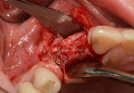

Clinical Cases

• Case1

• Case2

• Case3

• Case4

• Case5

• Case6

• Case7

• Case8

• Case9

• Case10